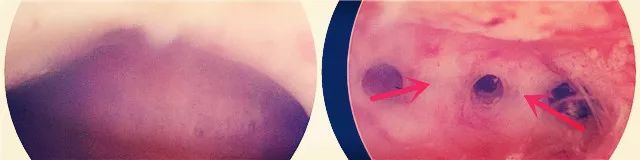

图中箭头处标记为宫腔镜下看到的宫腔粘连

宫腔粘连的诊断方法其实比较有限,最好的方法便是 宫腔镜检查 。它能够在直视下观察宫腔形态特征,了解粘连的性质、部位、程度和范围,同时还可进行治疗。子宫输卵管造影及宫腔声学检查也有一定诊断价值,但准确率远不及宫腔镜检查。另外有研究认为三维超声诊断宫腔粘连的敏感度可达100%,但其尚待进一步研究。其他检查如磁共振及二维超声对宫腔粘连的诊断价值则非常有限。